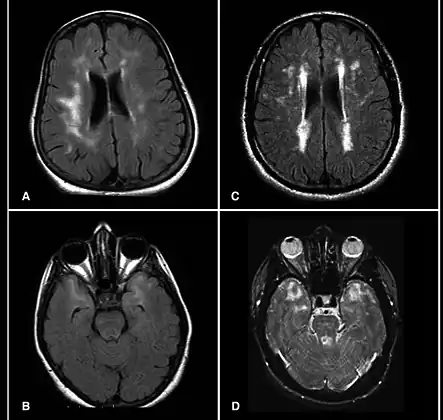

CADASIL is an inherited disorder caused by mutations in the NOTCH3 gene located on chromosome 19.[19] NOTCH3 codes for a transmembrane protein whose function is not well-known. However, the mutation causes accumulation of this protein within small to medium-sized blood vessels.[19] This disease often presents in early adulthood with migraines, stroke, mood disturbances, and cognitive deterioration. MRI shows white matter changes in the brain and also signs of repeated strokes. The diagnosis can be confirmed by gene testing.[20]